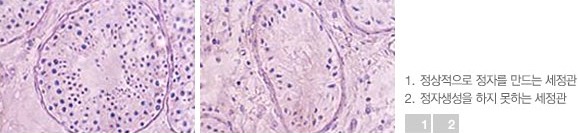

고환조직 검사